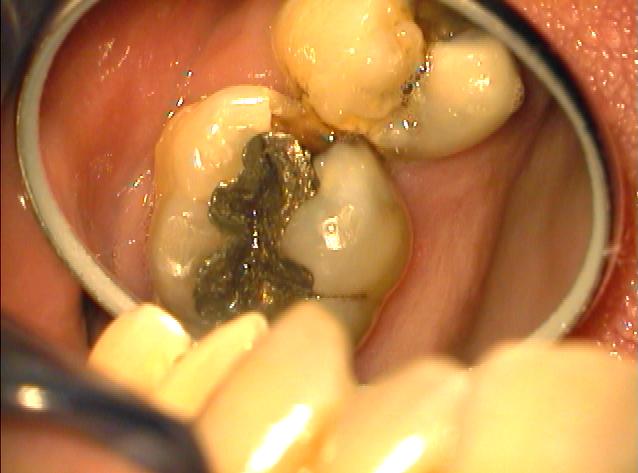

Klinische Ausgangssituation

Klinische Ausgangssituation zur gleichen Zeit